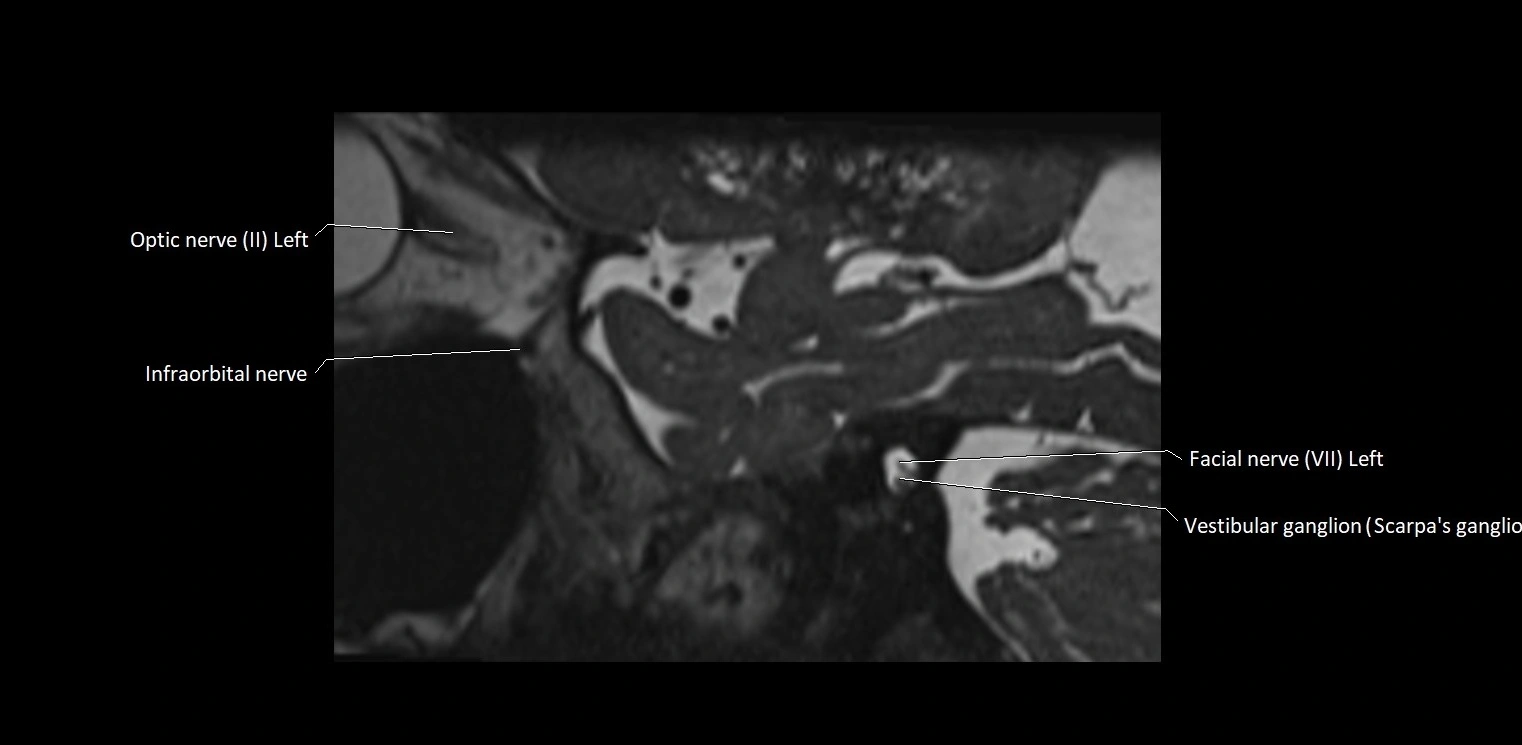

MRI Appearance

• The abducens nerve is a small, thin, linear structure

• Best visualized on high-resolution T2-weighted 3D MRI sequences (e.g., FIESTA or CISS)

• Seen as a hypointense (dark) line running from the brainstem at the pontomedullary junction, traversing the prepontine cistern, and entering Dorello’s canal under the petrosphenoidal ligament, then into the cavernous sinus, and finally the orbit

• May be challenging to visualize in standard MRI due to its small size

• Pathology may be inferred by absence, displacement, or enhancement of the nerve